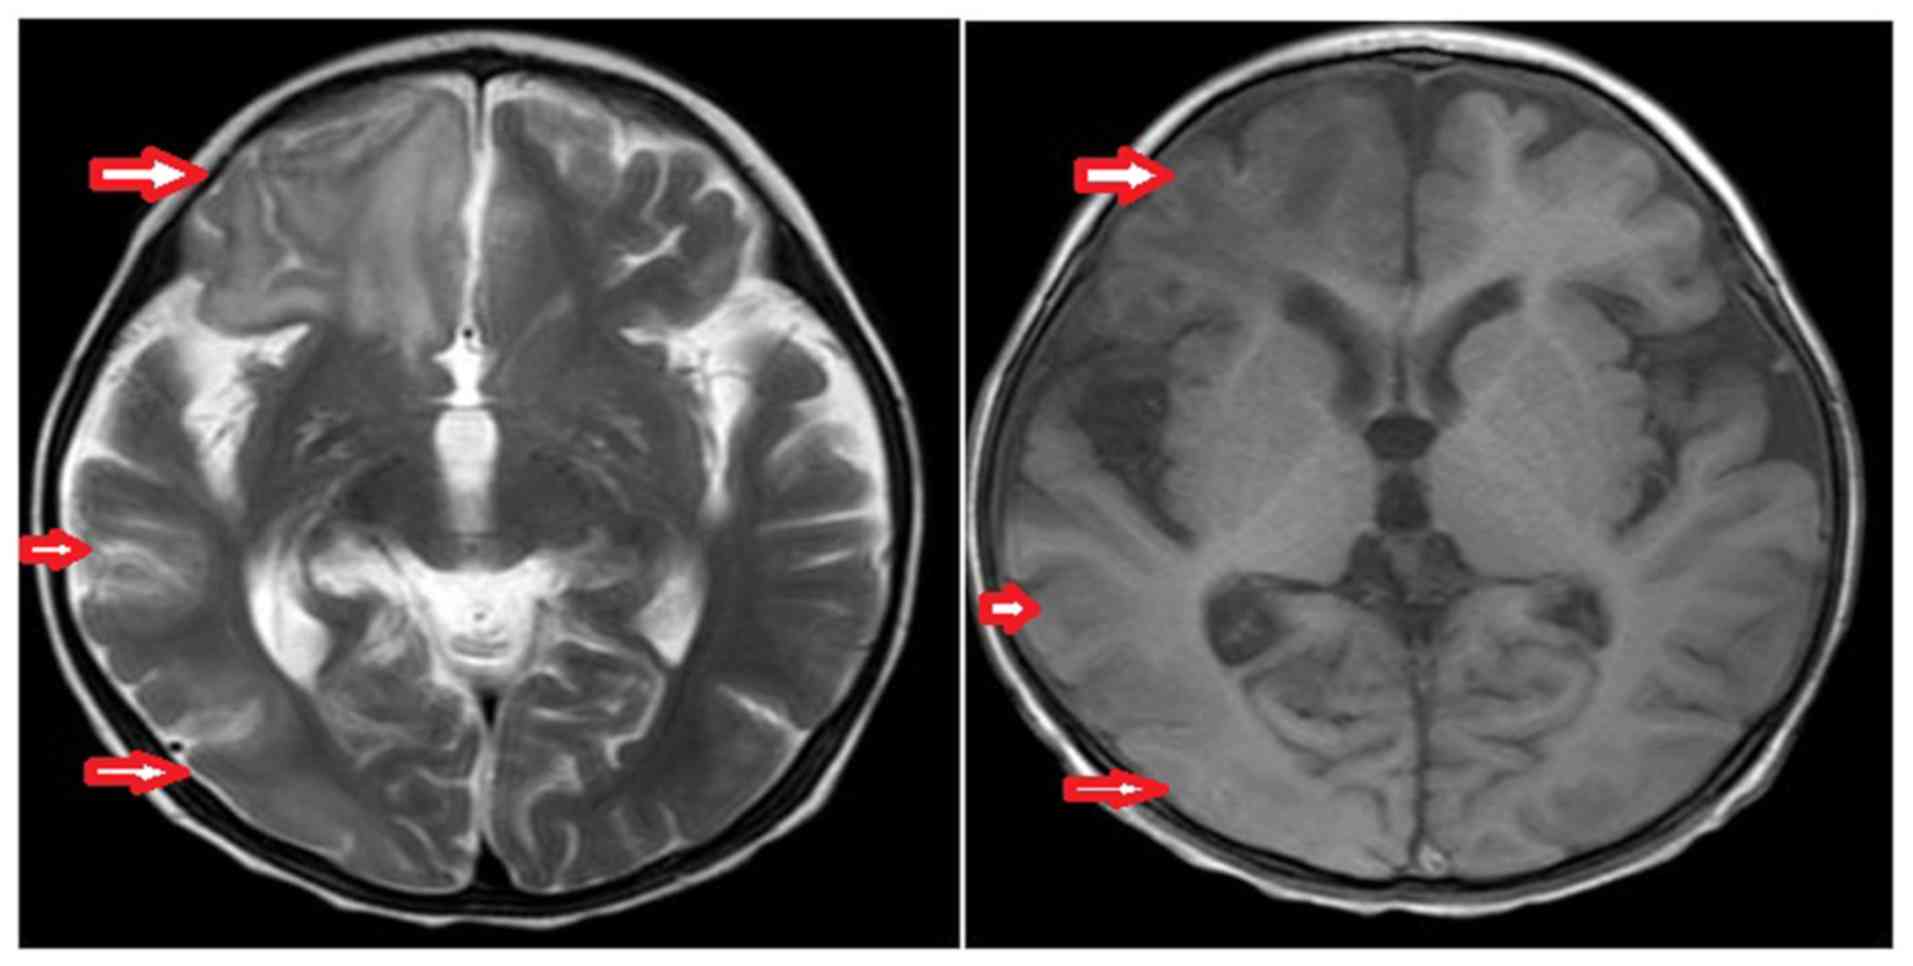

Primary carnitine deficiency in two sisters with intractable epilepsy and reversible metabolic cardiomyopathy: Two case reports

Primary carnitine deficiency (PCD) is a disorder of the carnitine cycle that results in defective fatty acid oxidation. When carnitine cannot be transported into the cells, fatty acid oxidation is impaired, resulting a variety of symptoms, such as chronic muscle weakness, cardiomyopathy, hypoglycemia and liver dysfunction. The clinical manifestations and outcomes of different cases with PCD vary among patients. The present case report focused on two sisters with PCD. The younger sister presented with intractable epilepsy, and the older sister presented with reversible metabolic cardiomyopathy. Potential mutations in the SLC22A5 gene were investigated within the family, and a nonsense mutation [c.760C>T (p.R254X)] was identified in four family members. The two sisters harbored homozygous mutations, whereas their parents presented heterozygous mutations. Metabolic disease screening revealed low plasma free carnitine levels (<5 µmol/l) in the two sisters. The plasma free carnitine levels of their parents were normal, and they were asymptomatic. PCD in the two patients was managed using oral levocarnitine. The metabolic cardiomyopathy of the older sister improved following 3 months of treatment. However, the epilepsy of the younger sister was recurrent with oral antiepileptic therapy lasting one year and eight months, and epilepsy was finally controlled following right cerebral resection. The present case report demonstrated that the clinical manifestations presented by patients with PCD within the same family were different. The results indicated that treatment with levocarnitine supplementation should be initiated as soon as possible before irreversible organ damage occurs. In addition, metabolic decompensation and cardiac muscle functions were improved following carnitine supplementation. The resection of the severely diseased unilateral brain combined with carnitine supplementation and antiepileptic therapy may be an effective treatment for PCD with intractable epilepsy complications.